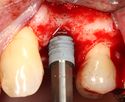

A series of slow-speed drills create and gradually enlarge a site in the jaw for the implant to be placed. The hole is called an osteotomy.

Once the bone is exposed, a series of drills create and gradually enlarge a site (called an osteotomy) for the implant to be placed.